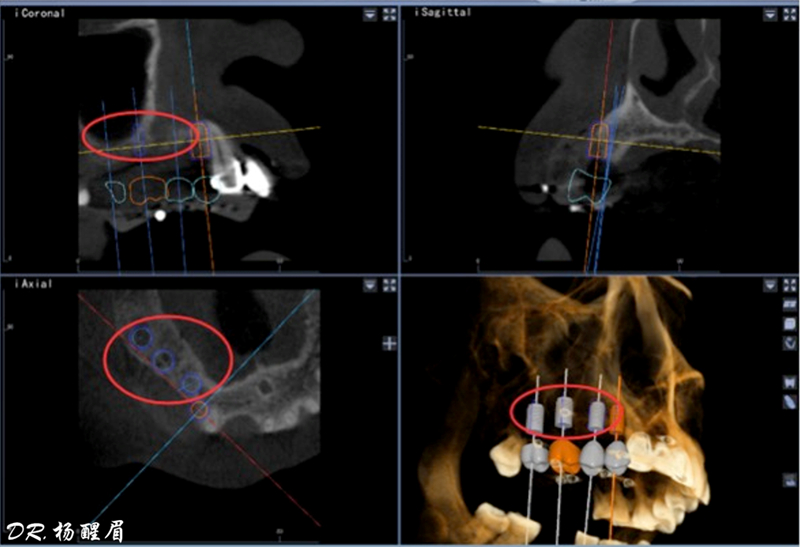

®使用迪凱爾易植美導航軟件進行方案設計,確定種植體使用方案,以及種植位點,方向和深度

®多顆植體種植方案應盡量保持軸向在同水平線上

®該患者需連續(xù)種植三顆植體,手術難度高。需保證相鄰植體位置關系符合種植要求。徒手種植難以保證其位置一致性。

®主刀醫(yī)生經(jīng)驗豐富,通過石膏模型排牙確定咬合關系,放射阻射材料提前放入缺牙區(qū),確定CBCT中牙冠位置,擺放種植體。遵循修復引導種植原則。

®如果翻瓣后發(fā)現(xiàn)患者實際情況與種植設計不符,迪凱爾易植美軟件能及時調(diào)整手術方案。主刀醫(yī)生使用導航軟件無需借助額外輔助工具,對種植過程中術區(qū)散熱以及開口度和視野都無影響。